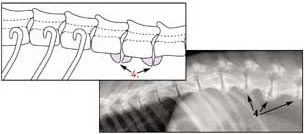

Die gesunde Wirbelsäule

1. Thoracic Rückenwirbel

2. Lumbar Rückenwirbel

3. Rippen

Rückenwirbel mit Spondylose

4. Krankhafte Knochenbildung am Rückenwirbel die anfängt zusammenzuwachsen